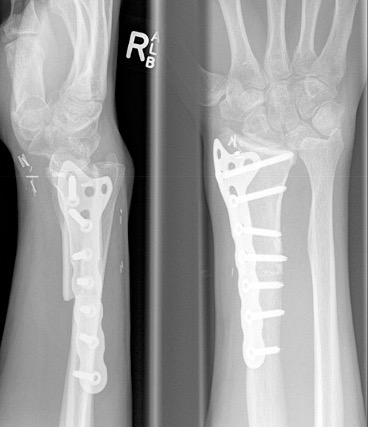

Distal Radius

Abuhejleh et al Eur J Orthop Traumatol Surg 2020

- 57 patients with GCT's of distal radius

- 29% (10/34) recurrence with intra-lesional treatement but no complications

- 4% (1/23) recurrence with wide resection / arthrodesis but 30% complication rate

- increased risk recurrence for Grade 3

- wide resection / arthrodesis should be reserved for grade 3

Koucheki et al Eur J Orthop Traumatol Surg 2023

- systematic review of 13 studies and 373 patients

- increased local recurrence with intralesional versus en-bloc resection

- especially Grade 3

- increased complications and poorer function with en-bloc resection

Distal radius GCT treated with en bloc resection and allograft reconstruction, followed by late wrist subluxation